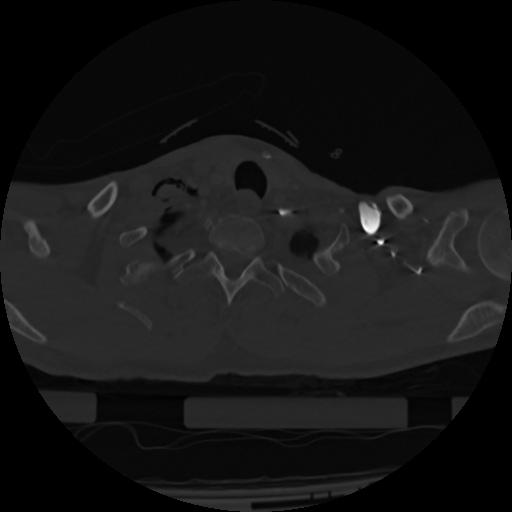

22 ANGIO,CE,Vol,0.5,ANGIO,,